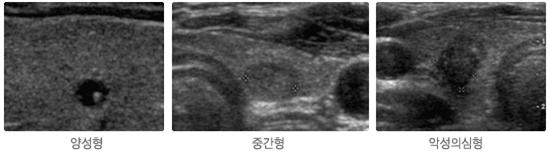

우먼플러스 산부인과 갑상선 결절에 대해 알아봤습니다! 갑상선 결절도 암에 걸릴 수 있는지 환자들이 굉장히 궁금해하고 있는데 실제로 갑상선 결절이 악성일 수도 있기 때문에 정확한 검사를 해봐야 합니다. 갑상선 결절 악성 여부를 진단하기 위해 초음파 검사, 미세침 흡인세포 검사 등을 실시하고 양성 결절로 진단되면 병원에서 안내하는 대로 정기적인 추적 관찰을 받는 것이 좋습니다. 갑상선 결절에 대한 자세한 내용은 언제든지 우먼 플러스 산부인과 의원에 문의하십시오. 감사합니다:)